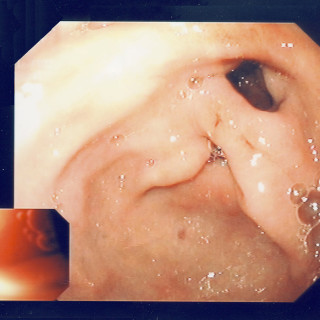

Pankreatitt hos barn kan være forårsaket av medikamenter, traumer, infeksjoner og systemsykdommer. Residiverende pankreatitt har ofte anatomiske eller arvelige årsaker. Italienske forskere ønsket å kartlegge årsaker til pankreatitt hos barn og vurdere bruk og nytte av bildeundersøkelser ved tilstanden (1). I en fem års retrospektiv studie ved et tertiærsykehus undersøkte man 34 barn, hvorav 23 gutter, i alderen 2 – 18 år (median 11 år). 11 hadde residiverende pankreatitt (1). De vanligste årsakene var legemidler, særlig azatioprin, og gallegangssykdommer. Ultralydundersøkelse av abdomen ble...